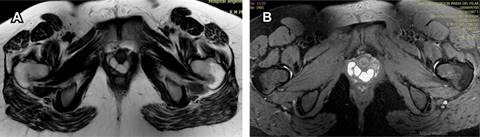

Figura 1: Resonancia magnética de pelvis axial (A) potenciada en T2 y (B) T2 FAT SAT. Se observan imágenes ovoideas de aspecto quístico que se localizan en el espesor de la pared vaginal anterolateral, sin disrupción del esfínter urinario.

Femenino de 31 años de edad que refiere abultamiento en región periuretral asociado con datos de disuria de dos semanas de evolución. Acude a médico particular, el cual refiere tumefacción parauretral con extensión a pared vaginal anterior y solicita estudio de resonancia magnética de pelvis contrastada, en la que se observan imágenes saculares bien delimitadas hipointensas en la secuencia T1 e hiperintensas en T2, de aspecto agrupado, que tras la aplicación de medio de contraste no presentan realce significativo, localizadas en el muro anterior del tercio distal de vagina con diámetros aproximados en el plano sagital de 1.9 cm, coronal 3.4 cm y axial 3.5 cm, situadas a 1.1 cm del introito vaginal y a 3 cm del cérvix uterino. La uretra se observa respetada sin datos de disrupción de los esfínteres. Impresión diagnóstica: imágenes quísticas en tercio distal y anterolateral de vagina que sugieren la posibilidad de quiste de Gartner (Figuras 1 y 2).